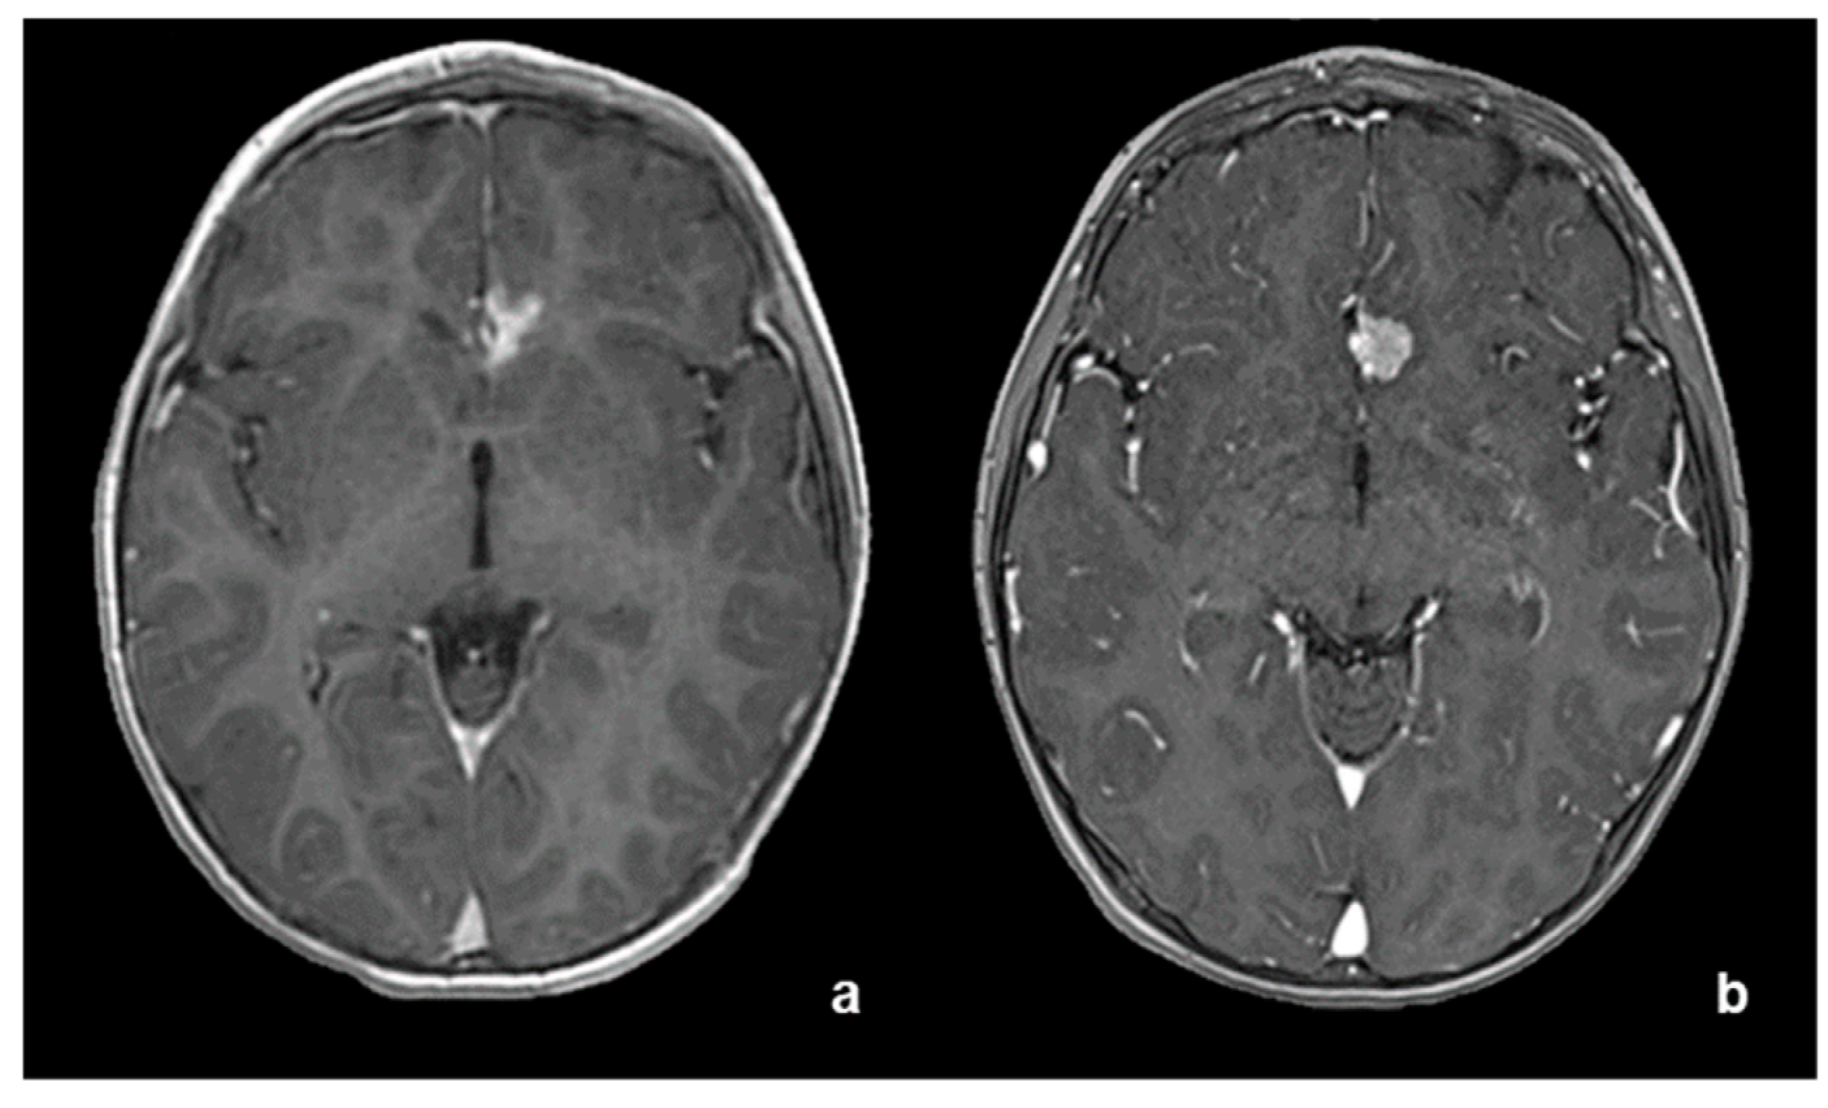

2. Case Report